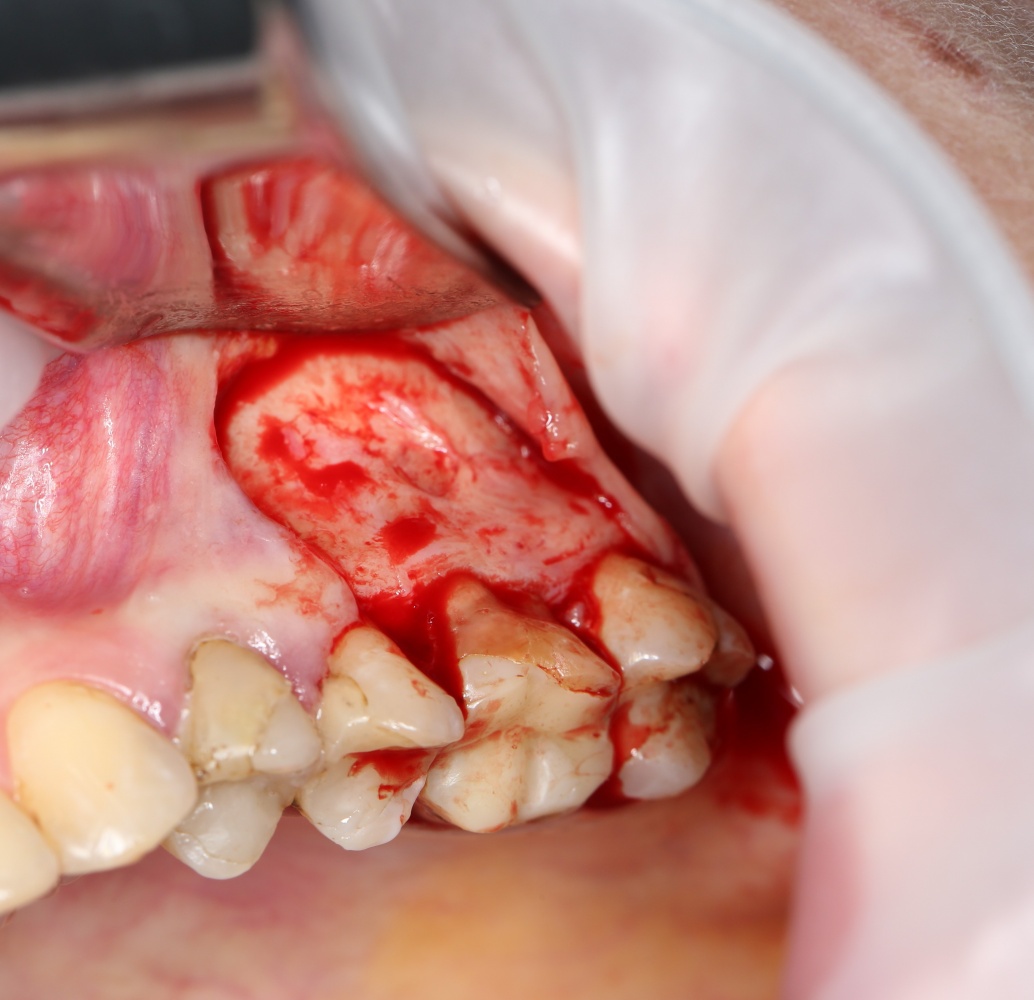

Вот клиническая картина через 4 месяца после ранее проведенной имплантации с остеопластикой:

Как видишь, коллеги из недалекой дружественной страны не осилили снятие швов. Мне это не нравится, хотя и объясняет, почему люди готовы ехать за тыщи километров ради 20-минутной операции удаления зуба мудрости.

Ну хорошо. Швы сняли. Делаем разрез. Обрати внимание, что после всех проведенных операций у нас остается очень небольшой по ширине слой жевательной слизистой оболочки: